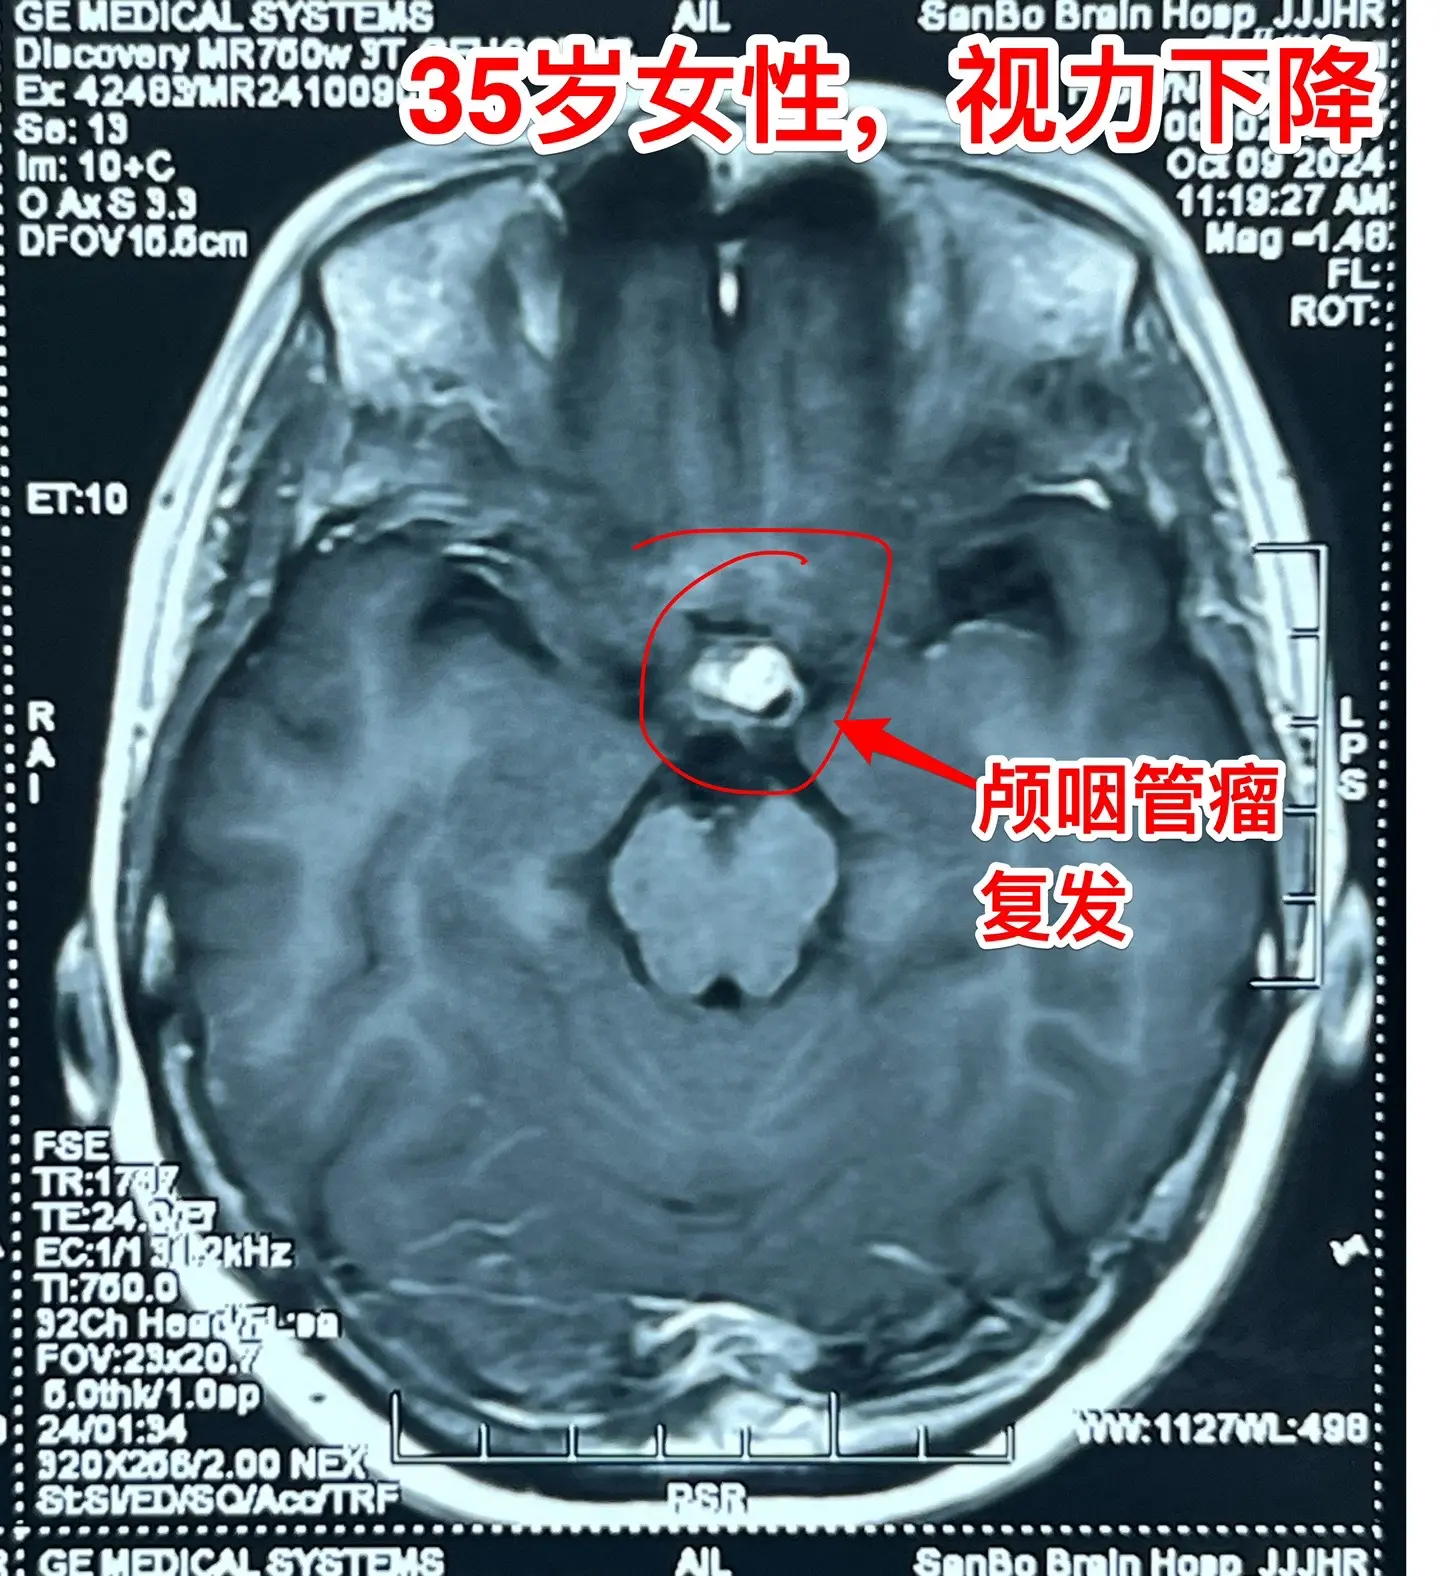

一天完成两个颅咽管瘤手术几乎成了常态。今天的两个颅咽管瘤手术,强度很大哦! 1,4岁男孩子,视力下降。典型的造釉细胞型颅咽管瘤,属于鞍隔下颅咽管瘤。开颅手术将颅咽管瘤完全切除,垂体大部分保留,垂体柄保留,下丘脑保护完好。这样的结果我们很满意! 2,35岁女性,经鼻手术后颅咽管瘤复发,视力下降。是乳头型颅咽管瘤。肿瘤与视交叉粘连很紧,手术分离难度大,最终得到完全切除。